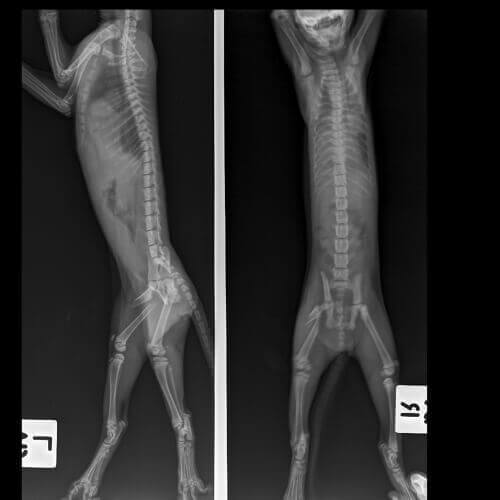

Diagnostyka kulawizny u kotów może wymagać przeprowadzenia specjalnych badań. Często obejmuje on jedną lub więcej z następujących analiz:

- Promienie rentgenowskie.